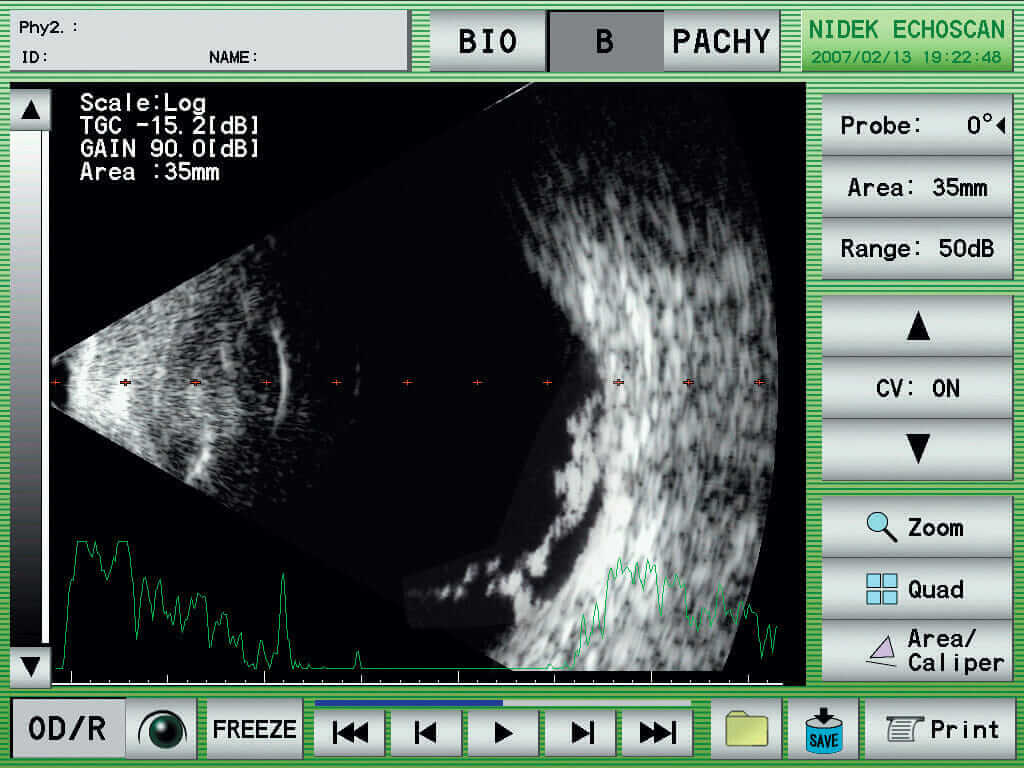

Nidek US-4000

Ultraschall A/B Scan mit Pachymtrie

Kompaktes, modular ausbaubares Instrument. Durch das kontrastreiche Display können B-Scan sehr gut auf dem Display live angesehen werden. Verschiedene Bearbeitungsprogramme lassen eine perfekte Lokalisation zu. Sehr einfache Bedienung durch den Touch Scren Bildschirm, schnelles abspeichern von Messungen, Druckmöglichkeit durch den integrierten Printer oder USB Interface für Datenexport. Zur Kalkulation von IOL und Patientenverwaltung. IOL Formula (SRK, SRK2, SRK-T, Binkhorst, Holladay